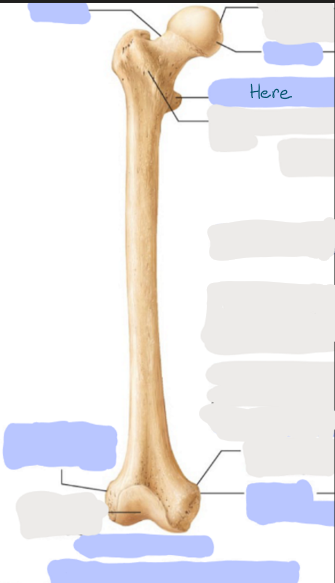

What is this picture of?

Anterior view of the Right Femur

What is here?

Where is the Neck of the Femur?

What is here?

Where is the Head of the Femur?

What is here?

Where is the Lesser Trochanter of the Femur?

What is here?

Where is the Lateral Epicondyle of the Femur?

What is here?

Where is the Medial Epicondyle of the Femur?